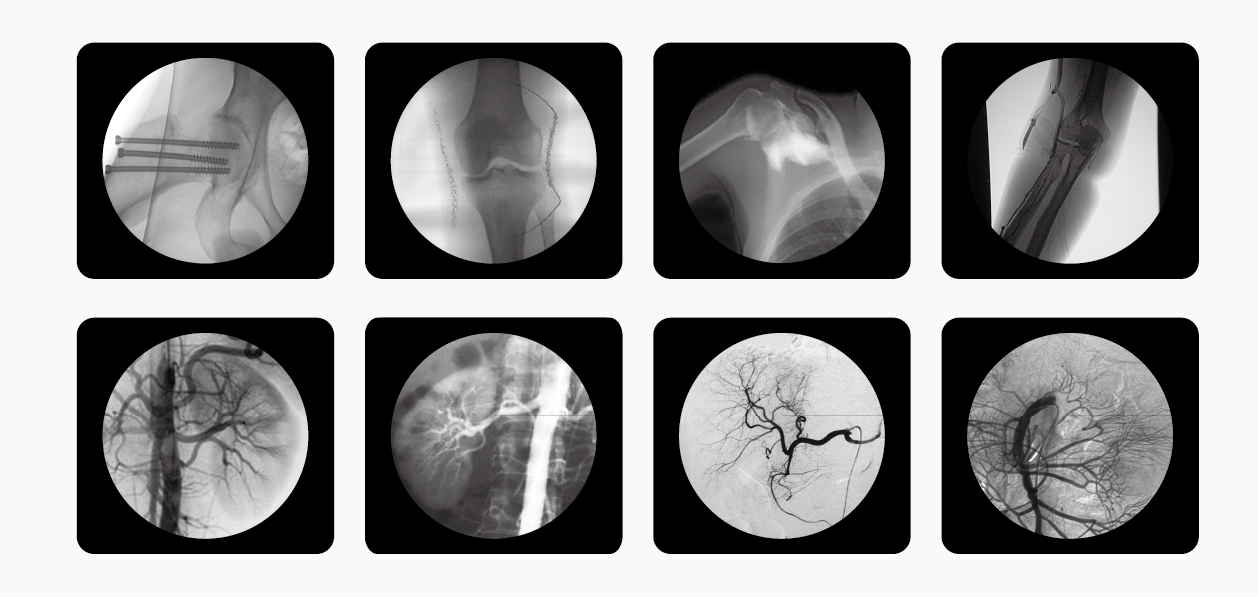

C型臂也就是我們所說的C臂機(jī)或C形臂X光機(jī)等,因?yàn)槠洫?dú)有的C型的機(jī)架而被這么命名,儀器主要由產(chǎn)生X射線的球管,采集圖像的影像增強(qiáng)器和CCD攝像機(jī),以及圖像處理的工作站組成,是現(xiàn)代臨床不可或缺的醫(yī)療輔助設(shè)備。

南京普愛醫(yī)療C形臂X光機(jī)是國內(nèi)眾多生產(chǎn)廠家中的一匹黑馬,該公司擁有多種型號的C形臂X光機(jī),其中PLX7000C被廣泛應(yīng)用于介入科、骨科、外科、矯形外科、泌尿外科、脊柱外科、腹部外科、疼痛科、心臟科、消化科、婦科及手術(shù)室等。

C形臂X光機(jī)

擁有更大功率的高壓發(fā)生器適合對肥胖病人的高密度組織進(jìn)行成像,并且也有更高熱容量的球館可以滿足長時間、大量手術(shù)的需要。多種工作模式,滿足各種臨床需要,多葉與垂直光影控制,有效減少軟X線,大幅降低皮膚劑量,其還配有進(jìn)口品牌影像增強(qiáng)器,全數(shù)字化CCD攝像機(jī),提供高分辨的優(yōu)質(zhì)圖像。

C形臂X光機(jī)PLX7000C整機(jī)性能如下:

1、數(shù)字化高頻發(fā)生器,采用微焦點(diǎn),利用射線劑量控制,滿足您的多種復(fù)雜臨床診治要求;雙面板人體圖形化液晶觸摸屏,操作智能快捷;雙運(yùn)動控制系統(tǒng)、雙曝光腳閘設(shè)計,極大滿足臨床操作;

2、全數(shù)字化百萬像素影像采集系統(tǒng),優(yōu)化設(shè)計和配置,為您提供高分辨率、高灰階圖像,支持您做出準(zhǔn)確診斷;

3、專用高清醫(yī)用液晶顯示系統(tǒng),呈現(xiàn)給您高亮度、高對比度的臨床圖像;對比自然,有益于診斷的圖像細(xì)節(jié)顯示更加清晰、層次更加豐富;

4、四維電動運(yùn)動控制,定位準(zhǔn)確,靈活自如;超大機(jī)架設(shè)計,提供了超大的診視空間,更加舒適的手術(shù)環(huán)境;全新設(shè)計,全新理念、帶來超凡體驗(yàn);

5、工作站具有大容量數(shù)字化存儲功能,透視和數(shù)字點(diǎn)片均以數(shù)字化格式無損存儲,邊緣增強(qiáng)多重鏡像 gamma校正、電影回放、窗寬窗位、專家模板、刻錄等強(qiáng)大處理功能。